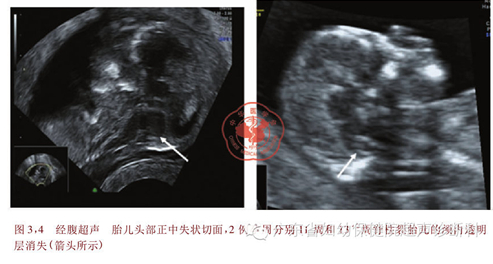

脊柱裂是胎儿常见的中枢神经管畸形之一,是由于在胚胎发育时期受某些原因影响而造成神经管不能闭合所致。脊柱裂在我国的发生率为0.274%,其中开放性脊柱裂占30.9%。尽管可以通过超声检查来诊断开放脊柱裂,但在孕14周以前由于病灶较小和常规超声检查胎儿解剖结构中缺乏可靠的颅骨和脑组织形态改变的间接征象(如“柠檬头”和“香蕉小脑”);另外,早孕期脊柱骨化未完全,超声难以直接观察脊柱的形态和排列异常等直接征象,目前筛查和诊断开放性脊柱裂胎儿大多在中晚孕期。超声在孕11~13+ 6周胎儿面部正中矢状面上测量颈项透明层(nuchal translucency,NT)已经作为筛查染色体异常的手段之一。在这个切面上,可以观察到位于脑干和脉络丛之间的第四脑室,由于第四脑室回声与颈项透明层相似,故命名为颅内透明层( intracranial translucency,IT) 。开放性脊柱裂胎儿脑组织向尾侧移位,导致第四脑室受压变小,而正常孕11~13+6周胎儿第四脑室清晰可见。本文通过几篇文献复习,与大家一起分享一个新的可能是更早期的诊断开放性脊柱裂的指标——颅内透明层(IT)。